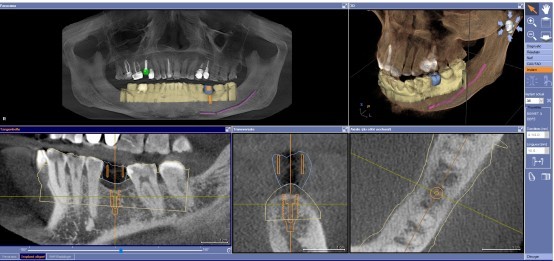

La sécurité d’abord avec la radiographie 3D (CBCT)

L’équipe du cabinet a toujours en tête votre sécurité et votre confort tout au long du traitement. Vous êtes un être en trois dimensions, et toute chirurgie implantaire doit être planifiée en 3D pour éviter l’imprécision lors du placement de l’implant ou la lésion d’importantes structures anatomiques.

Chirurgie guidée : prévisibilité et précision du traitement

Une fois que nous avons développé un plan de traitement personnalisé et décidé du positionnement des implants, nous utilisons des guides chirurgicaux pour nous assurer que chaque implant est placé exactement comme nous le voulons, avec une grande précision et une grande sécurité.

Ces guides sont fabriqués à partir de la planification 3D virtuelle de vos implants et sont imprimés par nos imprimantes 3D.